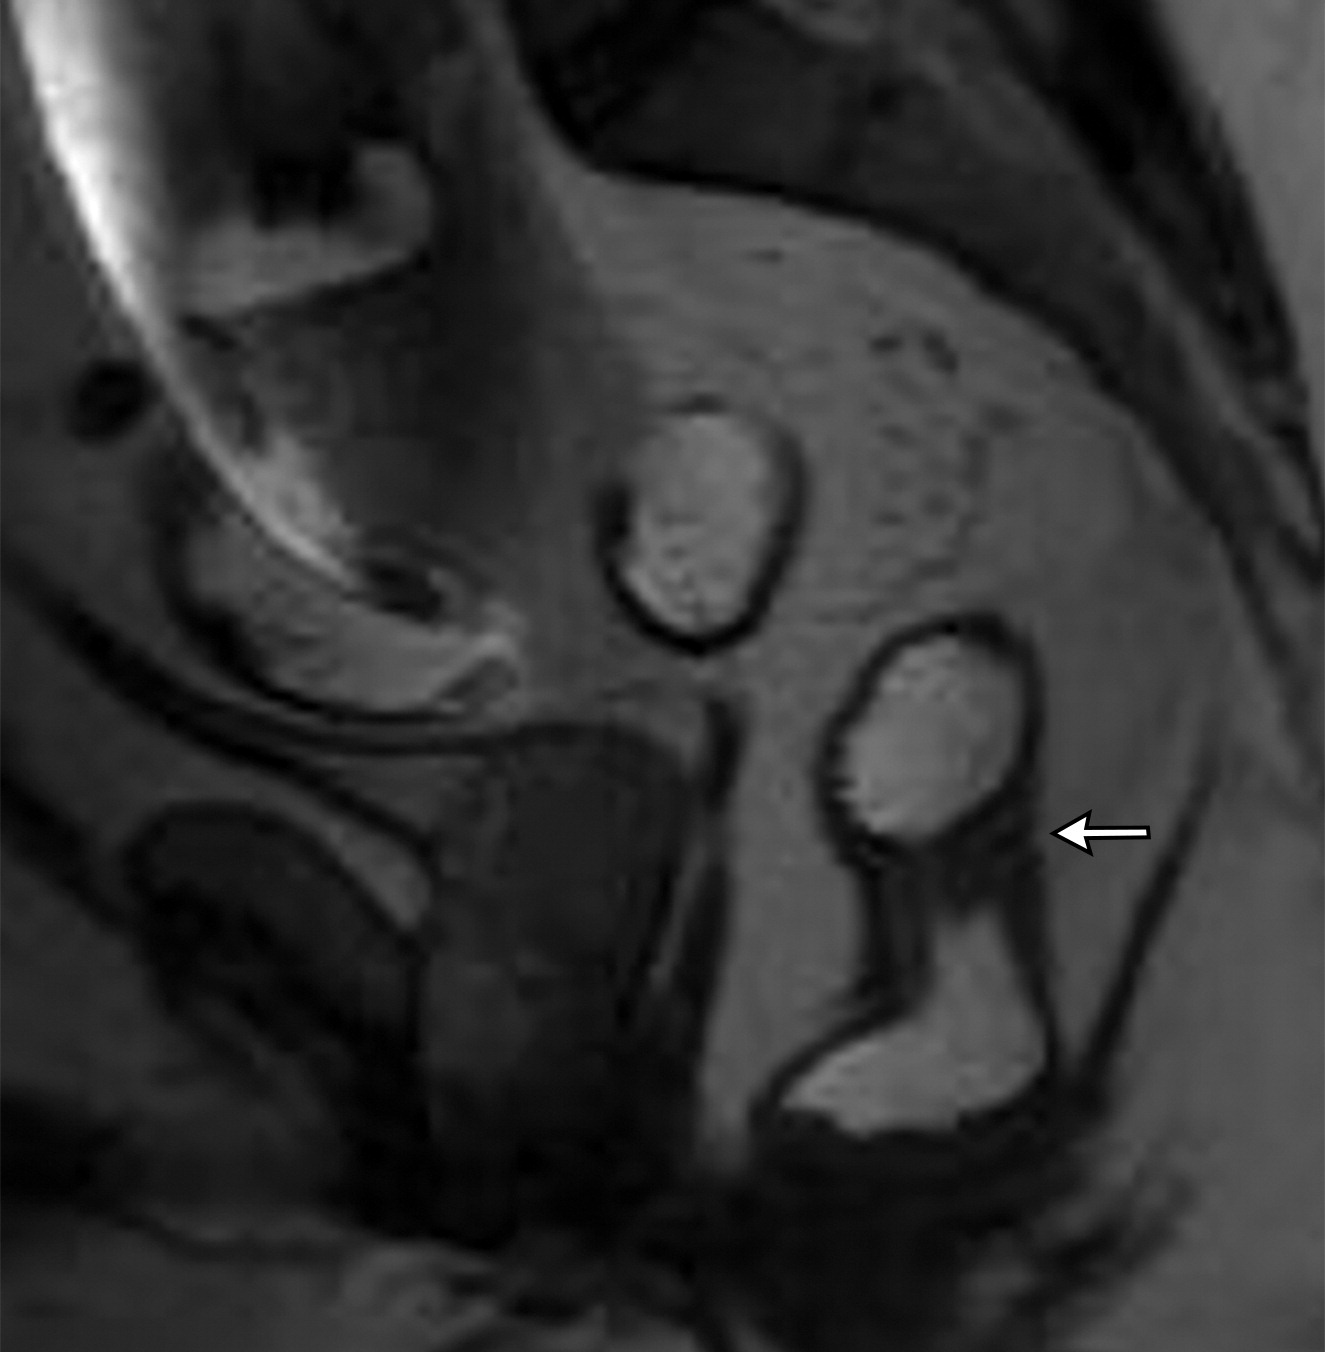

50岁以上男性骨盆和盆底的MRI解剖。

提肛肌(LA),由耻骨直肠肌(PR)、耻骨尾骨肌(PC)和髂尾骨肌(IC)组成;尾骨肌(C),前列腺(P),闭孔内肌(OI),会阴浅横肌(STP),球海绵体肌 (B), 坐骨海绵体肌(ISC),肛门外括约肌(EAS),肛门内括约肌(IAS),直肠(R),尿道括约肌(SU),也称为尿道外括约肌(U),它包围着整个膜性尿道。6774449af17bb1b8df6e83ab4e9fa158.jpeg